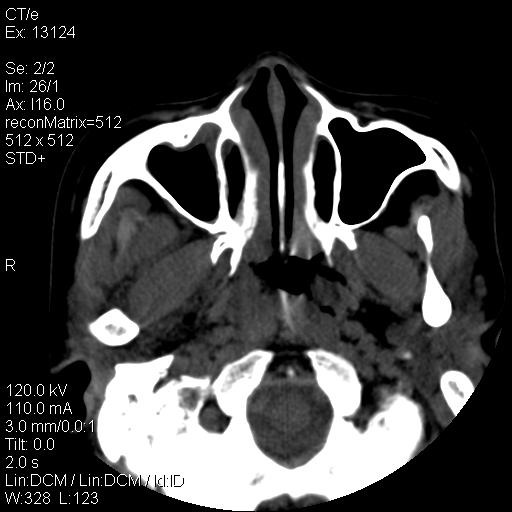

标题: CT18257:女,29岁,右下磨牙痛 [打印本页]

标题: CT18257:女,29岁,右下磨牙痛

女,29岁,右下磨牙痛,因产后2月,故未治疗。现右颌肿痛伴张口困难。请大家看看右侧鼻咽部、口咽部是否

2.右侧上颌窦炎症、两侧下鼻甲肿大

考虑----扁桃体炎症并脓肿形成及周围唾液腺-咽部-右上颌窦炎症,抗炎后复查。

1)考虑右侧下颌区软组织脓肿(牙源性)。2)鼻咽部炎性改变;建议追踪复查。3)右侧上颌窦炎。4)双侧下鼻甲黏膜肥厚。

1)考虑右侧下颌区牙源性软组织脓肿。2)右侧上颌窦炎。3)双侧下鼻甲黏膜肥厚。4)鼻咽部炎性改变;建议追踪复查。